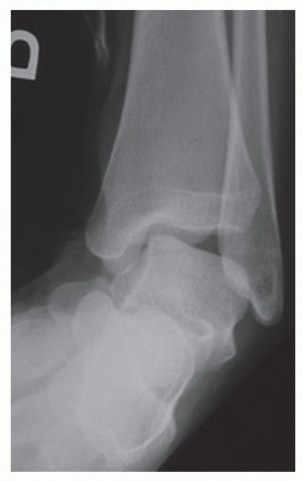

DEFINITION Osteochondral lesions of the talus (OLT) are common conditions that can involve both the cartilage…

DEFINITION The term osteochondral lesion of the talus (OLT) refers to any pathology of the talar articular ca…